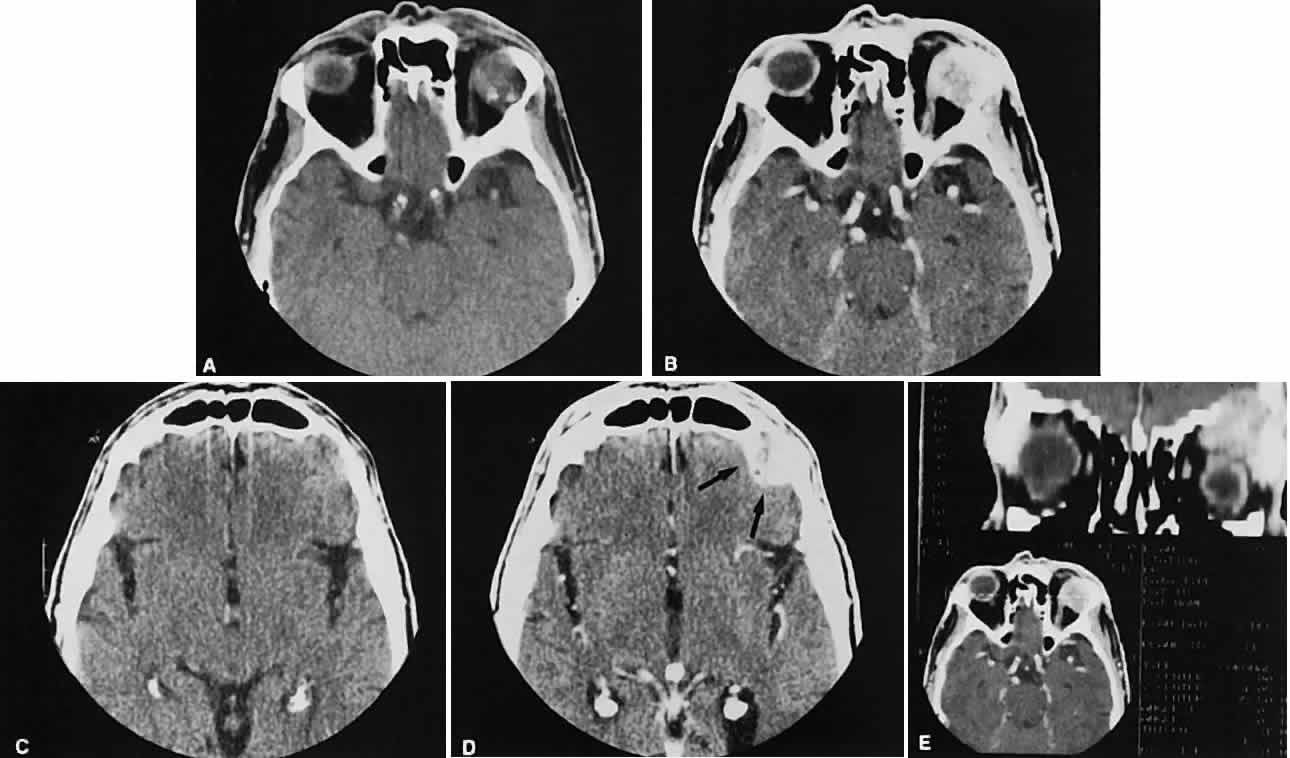

After the orbit has been visualized adequately, it also has been our practice to obtain 10-mm axial slices through the remaining portion of the head to complete the study. Intravenous contrast material usually is given, although the low-density orbital fat produces an inherent high level of contrast for most orbital CT studies. Intravenous administration of iodinated contrast medium is most helpful in detecting intracranial extension of an orbital process or identifying a pathologic process involving the optic nerve/sheath, most notably optic nerve sheath meningioma. Specific contraindications for contrast material include allergy or renal failure.

An appreciation for the various pathologic processes that affect the orbit is facilitated by an understanding of the normal orbital anatomy (Fig. 1). The orbit is a pyramid-shaped bony structure bounded inferiorly by the maxillary sinus, medially by the ethmoidal sinus, and superiorly by the frontal sinus. The sphenoidal sinus is situated posteriorly along the medial orbital wall and has a common wall with the optic canal. The lacrimal gland lies within its fossa located in the superior temporal aspect of the orbit and can be seen on both axial and coronal views.

The extraocular muscles (EOMs), with the exception of the inferior oblique, originate from the anulus of Zinn in the orbital apex. The inferior oblique takes its origin from the frontal process of the maxilla and is seen occasionally on CT imaging. The superior oblique, after originating from the anulus, courses along the superior nasal orbital wall just above the medial rectus muscle before passing through the trochlea. The rectus muscles conveniently form a muscle cone, which is sometimes helpful in terms of differential diagnosis. Before thinner axial slices and multiplanar imaging were available, an enlarged inferior rectus muscle often was imaged as an apical mass, especially if dysthy-roid optic neuropathy was present. The importance of imaging from two different planes cannot be overemphasized in this situation.

The superior ophthalmic vein (SOV) is an important vascular structure to recognize. It begins in the superior nasal quadrant near the trochlea before coursing posteriorly and laterally beneath the superior rectus muscle, exiting the orbit through the superior orbital fissure. Drainage is into the cavernous sinus. Asymmetric enlargement, especially in the presence of an ipsilateral cavernous sinus enlargement, suggests a vascular anomaly, which may require selective carotid angiography for further definition. Enlargement of one or multiple EOMs in this setting is likely. The SOV also may be enlarged as a result of any process impeding drainage from the orbital apex, such as dysthyroid orbitopathy or metastatic disease.

The optic nerve occupies the central intraconal space. By necessity, the nerve has a certain amount of slack, which is necessary to permit movement of the globe. In the axial plane, the optic nerve has an undulating course and thus may appear thicker or thinner as a result of partial volume averaging as it passes in and out of the axial plane. It is imperative to recognize this normal pattern for proper interpretation of axial images.

The optic nerve itself is invested by the same meningeal layers that cover the brain, and the intracranial space may extend along the course of the optic nerve to the back of the globe. Enlargement of this space may be recognized as pseudomeningoceles of the optic nerve sheath. It is sometimes possible to tell whether the nerve, the sheath, or both are enlarged by CT scanning, although MRI affords the better view.